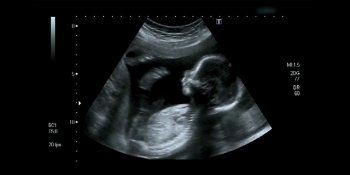

Tijekom ultrazvuka, roditelji su vidjeli nešto neočekivano - dječakovu malenu ruku kako drži prst svoje sestre.

Ona je sačuvala fotografiju sa ultrazvuka, koja će joj, kako kaže, u budućnosti služiti kao dokaz da su se njena djeca neizmjerno voljela.